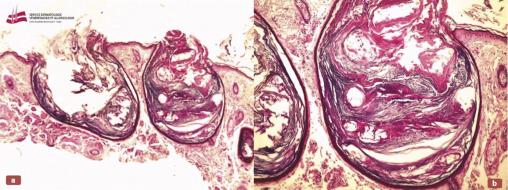

Ce patient de 71 ans, fumeur suivi pour une amylose AL (amylose primitive, à chaînes légères d’immunoglobulines) associée à un myélome multiple, était sous chimiothérapie et acide zolédronique. Il avait développé, depuis plus d’un an, plusieurs lésions kystiques et comédoniennes étendues de la face et du cou, plus marquées sur le front et les régions temporales, avec quelques comédons au niveau des joues, des rides et des sillons profonds du front, évoquant, entre autres diagnostics, un mycosis fongoïde pilotrope (fig 1 et 2). L’examen histologique de la biopsie cutanée était en faveur d’une élastoïdose de Favre-Racouchot (fig 3).

La maladie de Favre-Racouchot, ou élastoïdose nodulaire à kystes et comédons, est caractérisée par le développement de kystes et de comédons ouverts sur une peau endommagée par l’actinisme.1 Ses causes restent incertaines, bien que l’exposition au soleil, le tabagisme et les radiations ionisantes paraissent jouer un rôle.2 Son diagnostic est essentiellement clinique. Histologiquement, les lésions se caractérisent par une élastose ­actinique significative, une atrophie épidermique, une dégénérescence basophile du derme supérieur, des follicules dilatés et de gros kystes dans le derme moyen et inférieur. Les glandes sébacées sont habituellement atrophiques ou absentes.1 Divers traitements peuvent être proposés (rétinoïdes topiques, laser...). Une protection solaire et l’arrêt du tabac sont fortement recommandés.2